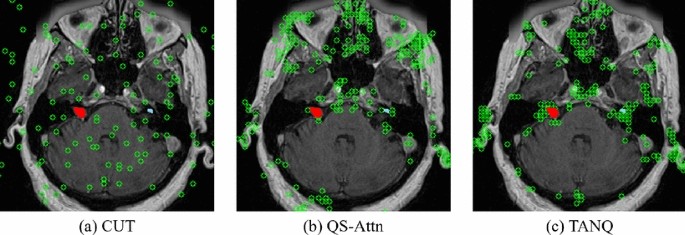

Informative patch selection

The locations of the selected patches for contrastive learning in (a) CUT16, (b) QS-Attn18, and (c) our TANQ are visualized with green indicators in Fig.5. It can be observed from Fig. 5(a) that CUT selects patches arbitrarily. This visualization demonstrates that such random selection tends to select patches from the background area as well, rather than focusing on specific anatomical structures of the brain, resulting in the lack of crucial information regarding brain structure, including the VS and cochlea. Numerous studies have also noted that using these “easy” negative samples for contrastive learning can result in poor performance in image translation tasks18,50,51.

In contrast, Fig. 5(b) illustrates that QS-Attn effectively calculates the contrastive loss by selecting features from regions that represent the structural information of the brain. Despite these advantages, Fig. 5(b) indicates that QS-Attn tends to struggle with feature selection in smaller VS (red) and cochlear (sky-blue) regions. In contrast, Fig. 5(c) demostrates a significant increase in the patch selection related to the regions of VS and cochlea, indicating a stronger focus on the VS and cochlea than in QS-Attn. This proves that our TANQ is remarkably effective with its target-aware normalization in preventing information loss in the VS and cochleas, guaranteeing the selection of patches specifically associated with these regions. Our framework generates more realistic pseudo-\(\text {hrT}_2\) images by focusing on the target objects during image translation for more efficient and effective contrastive learning techniques. Consequently, this approach enhances the performance of the segmentation model by obtaining suitable pseudo-\(\text {hrT}_2\) images.